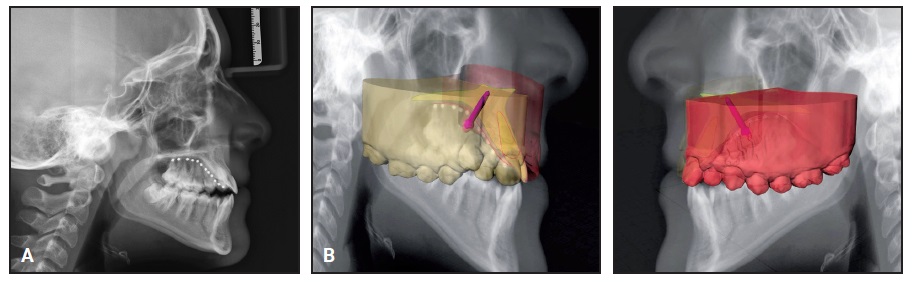

Digital intraoral scans were stored in STL format. When the lateral cephalogram was taken, a thermoplastic glycol-modified polyethylene terephthalate maxillary appliance with radiopaque markers positioned along the palatine raphe was used to identify the palatal mucosa and maxillary bone (Fig. 2A). According to Kim and colleagues, the accuracy of a lateral headfilm is comparable to that of a CBCT scan in determining the palatal thickness within 5mm of the median sagittal plane.26 After accurate matching of the lateral cephalogram with the digital models, the ideal direction of insertion, position, and length of two palatal miniscrews were determined (Fig. 2B).

Fig. 2 A. Fit of thermoplastic appliance. B. Accurate matching of lateral cephalogram with digital models for planning of miniscrew insertion.